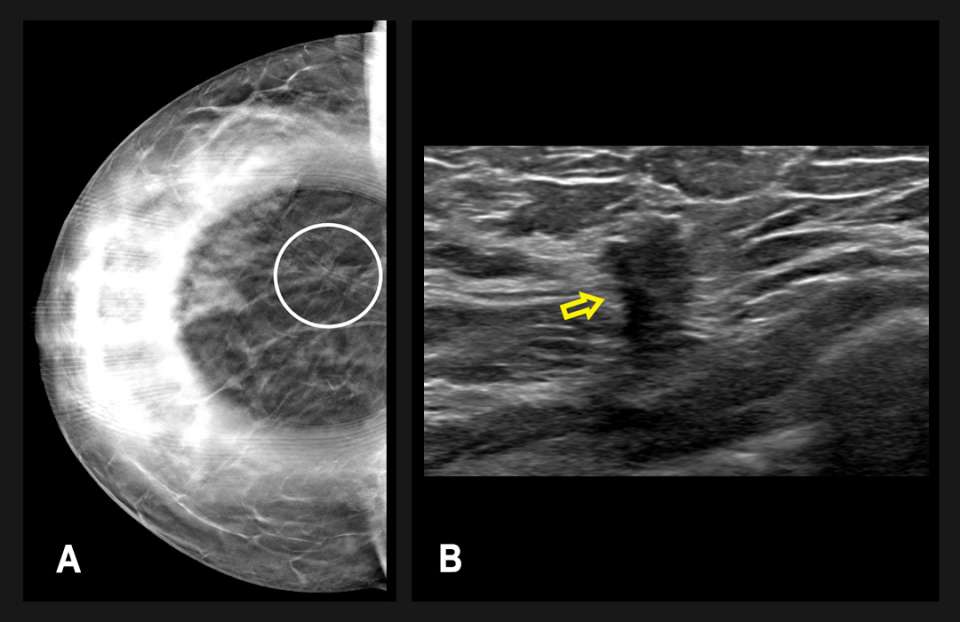

The screening mammogram demonstrated an area of architectural distortion in the lower outer quadrant of the right breast (Figure 1). By the Tyrer-Cuzick version 8 risk calculator, the patient was high-risk, with an approximate 20.3% lifetime risk of developing breast cancer. The mammographic findings were categorized as a BI-RADS 0, and the patient was called back for a diagnostic mammogram with possible diagnostic breast ultrasound.

Figure 1: (A) Right breast tomosynthesis craniocaudal (CC) and (B) mediolateral oblique (MLO) view images from a screening mammogram of a 42-year old patient. There is an area of architectural distortion (circled) in the lower outer quadrant, located 9 centimeters from the nipple. Diagnostic mammography was recommended.